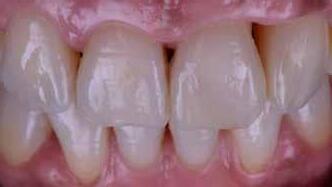

A fogászati kezelések során manapság már nem kizárólag az esztétikai megjelenés helyreállítására törekszünk. Sokszor a kedvezőtlen esztétikai megjelenés hátterében álló okok következményes módon a fogazat funkcionális működését is károsítják, így a kezelések során ezeknek a helyreállításával is foglalkoznunk kell. A különböző funkcionális és esztétikai diszkrepanciák kezelésére számtalan módszer létezik, ám ezen fogászati beavatkozások mindegyikében közös, hogy a kivitelezésük során nagyon szoros együttműködésre van szükség a kezelést végző fogorvos és a munkáját segítő fogtechnikus között. Az alábbi esetbemutatás során egy fiatal hölgypáciens fogazatának héjak alkalmazásával történő esztétikai és funkcionális rehabilitációját szeretnénk ismertetni.

A páciens fogazata esztétikai megjelenésének és funkcionális működésének a lehető legtöbb, saját foganyag megtartása mellett történő helyreállítása (1. és 3. ábra).

Az eddigi tapasztalataink szerint a páciensek jelentős többsége egyértelműen kifejezi az elégedettségét, ha a mock-up megfelel az eredeti elképzeléseiknek. A bemutatásra kerülő esetben is ez történt. A tervezett végeredmény megtekintését követően a páciens azonnal kérte az általunk javasolt kezelési tervben ismertetett beavatkozások elvégzését. A héjak alapanyagául az Ivoclar Vivadent által gyártott A1-es színű Telio CS kerámiát javasoltuk. Az anyagválasztás hátterében az állt, hogy ez az anyag nagy keménységgel rendelkezik, valamint az, hogy a felszínét nagy simaságúra lehet polírozni. A páciens rendkívül fiatal életkora is azt a terápiás koncepciót erősítette, hogy a kezelés során lehetőség szerint kizárólag non-invazív beavatkozásokat alkalmazzunk.

A páciens már kezdetben is rendkívüli érdeklődést mutatott a preparálást nem igénylő (non-prep), héjakkal történő ellátással kapcsolatban. Ennek a terápiás modalitásnak az előnyei közé tartozik, hogy a fogakat egyáltalán nem, vagy csak minimál invazív módon kell preparálni, nincs szükség ideiglenes héjak készítésére, a héjak alapanyagául szolgáló kerámia nem hajlamos az elszíneződésre, nem jellemző a beavatkozások elvégzését követően jelentkező posztoperatív szenzitivitás, valamint hogy ezzel a módszerrel rendkívül kedvező esztétikai végeredményt lehet elérni. A fenti előnyök rendkívül meggyőzően hatottak a páciensre. A döntése során azt is figyelembe vette, hogy amennyiben ezeket a viszonylag költséges restaurátumokat választja, akkor ez a kezelés végösszegét is jelentős mértékben befolyásolja.

A kezelés során az jelentette a legnagyobb kihívást, hogy a héjakkal ellátott fogak élethűen utánozzák a természetes fogazat megjelenését. A fogpótlás színének, valamint a restaurátumok felszíni textúrájának és alakjának harmonikusan kell a páciens arcesztétikájához és karakteréhez illeszkednie.

A platinafólia technikát 1896 óta alkalmazzák. Napjainkra az eredeti eljárás már kismértékben módosításra került, de lényegében ugyanazzal a módszerrel történik a platinafóliára készülő koronák és héjak elkészítése. A minimál invazív fogászat egyre szélesebb körben történő elterjedésének köszönhetően ez az eljárás a reneszánszát éli. A pácienseink egyre gyakrabban szeretnék a fogaik alaki, színi vagy helyzeti rendellenességeit a lehető legkisebb saját foganyagveszteség árán korrigáltatni. Az eljárás során 0,025 mm vastag 99,9%-os tisztaságú platinafólia kerül alkalmazásra. Amennyiben a megfelelő technikai háttér és a beavatkozások elvégzéséhez szükséges elméleti és gyakorlati szaktudás is rendelkezésünkre áll, akkor semmi sem állhat az utunkba a pácienseink új mosolyának kialakítása során.

A módszer első lépéseként a gipszből kiöntött csonkokat platinafóliával borítjuk (5. ábra). Az adaptálását követően a felhelyezett fóliát óvatosan eltávolítjuk, felhevítjük, majd ismét visszahelyezzük a csonkokra. Ezt követően történik meg az első kerámiaréteg felvitele (Waschbrand). Az első égetés során csupán egy nagyon vékony réteg kerámia kerül a fólia felszínére (6. ábra). Amikor az égetést követően ezt

a kezdetleges kerámiavázat visszahelyezzük a csonkokra, a kerámia anyagában vékony repedések alakulnak ki. A végleges restaurátum elkészítéséhez szükséges kerámia „köpeny” ekkor áll készen a további kerámiarétegek felvitelére és kiégetésére (opaker réteg, dentin- és zománcmassza felvitele) (7-10. ábra). A készülő fogpótlás végső formai megjelenése rétegenként kerül kialakításra.

A második égetés során szintén csupán egy nagyon vékony réteg transzlucens opalmassza kerül felhelyezésre. A restaurátum formai megjelenésének és a felszíni textúrák kialakítására csak ezt követően kerül sor. A fényégetés során nem alkalmazunk glazúrmasszát. A készre vitel során elérni kívánt, magas fényű polírt kézi eszközök alkalmazásával alakítjuk ki. A restaurátumok végső kidolgozását követően a platinafóliát egy csipesz segítségével óvatosan eltávolítjuk, majd a kifejezetten vékony héjakat a kontroll mintára helyezzük. Ezt követően a pótlások megfelelő illeszkedésén kívül a funkcionális elmozdulások közben kialakuló érintkezéseket és a kontaktpontokat is ellenőrizzük. Az ilyenkor esetlegesen szükségessé váló korrekciók elvégzésére a Ducera® LFC (Dentsply Sirona) kerámiaanyagot használjuk. A kész munka fogorvosi rendelőbe való szállítása előtt kifejezett jelentőséggel bír az elkészült restaurátumok gondos becsomagolása. Az átadni kívánt fogpótlások sérülésmentes szállíthatóságának biztosítása elengedhetetlen az eddigi munkánk védelme szempontjából.

A héjak átadását követően kialakuló állapot valósághű módon történő bemutatása érdekében próbapasztát alkalmaztunk (Try-In-Paste; Variolink® Esthetik Try-In-Paste, Ivoclar Vivadent) (11. ábra). A próba során ellenőrizzük a héjak színét, formáját és transzparenciáját. A próbapaszta alkalmazásának egyik lényeges pontja, hogy a paszta színe egyezzen meg a végleges beragasztás során alkalmazni kíván ragasztóanyag színével. A héjak végleges rögzítése során mindig adhezív rendszereket használunk.

nak megfelelően – előkészítjük (orthofoszforsavval történő savazás, lemosás, szárítás és bond réteggel történő fedés). Ezzel egyidejűleg a ragasztásra kerülő héjak is előkészítésre kerülnek (hidrofolysavval történő savazás, lemosás, szárítás, szilanizálás, bond réteggel történő fedés, és végül az alkalmazni kívánt ragasztóanyag felvitele). Ezután a héjakat a fogak felszínén egyesével pozicionáljuk, majd néhány másodpercen keresztül polimerizációs lámpa segítségével megvilágítjuk. Ezt követően a kifolyó ragasztófelesleget eltávolítjuk, majd elvégezzük a restaurátumok végső polimerizálását. A héjak végleges rögzítését követően az esetlegesen visszamaradt ragasztómaradványok eltávolításra kerülnek, valamint ellenőrizzük az okklúzió és artikuláció közben létrejövő fogérintkezéseket. Az optimális esztétikai eredmény biztosítása érdekében kiemelt jelentősége van a papillák helyreállításának (rózsaszín esztétika). A modern fogorvoslás egyik kiemelt célja a fehér- és rózsaszín esztétika közti harmonikus egyensúly megteremtése. A papillák színe, nagysága és szimmetrikus megjelenése meghatározó szerepet tölt be a rózsaszín esztétika kialakításában. Az íny lefutása ugyancsak rendkívül jelentős mértékben befolyásolja a páciens fogazatának esztétikus megjelenését.

A cikkünkben bemutatásra kerülő eset ellátása során preparációt nem igénylő héjak készítése mellett döntöttünk. A héjak készre vitele során a platinafólia technikát alkalmaztuk. Annak ellenére, hogy az elkészítésre kerülő héjak rendkívül vékonyak, és ezáltal a végleges rögzítésük előtt jelentős törésveszéllyel állunk szemben, összességében mégis olyan minimál invazív kezelési eljárásnak számítanak, amely segítségével kifogástalan esztétikai eredményeket lehet elérni. A fent leírtak alapján bátran javasoljuk e módszer alkalmazását.